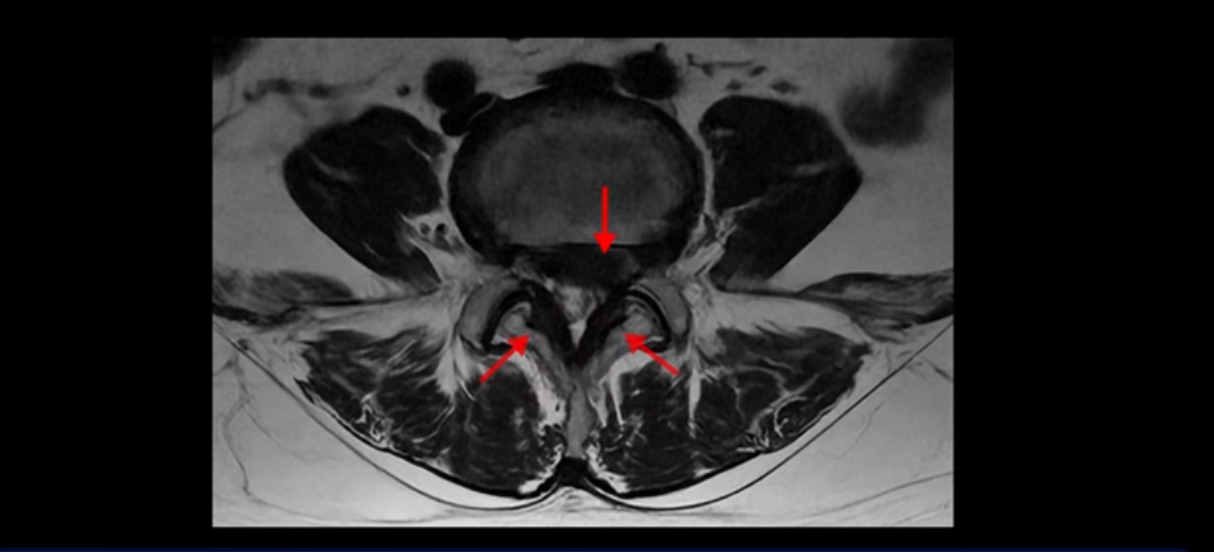

단면을 보면 디스크 수핵은 왼쪽으로 심하게 밀려 나와 있고

좌우 뒤쪽에는 황색 인대가 두꺼워져 있습니다.

앞에서는 디스크 수핵이 신경 공간으로 침범하고 뒤에서는 두꺼워진 인대가 신경 공간을 좁히고 있습니다.

이렇게 신경 공간이 좁아진 것을 협착이라고 합니다. 왼쪽으로 신경 구멍이 더 좁아져 있으니까 처음에는 왼쪽 엉덩이와 다리가 아팠는데 몇 년 동안 주사 맞으면서 버티다 보니까 오른쪽 다리까지 아프게 됩니다. 결국 양쪽 다리가 너무 아파서 5분 걷기도 힘들어지게 됩니다.

걸을 수 있는 거리는 점점 짧아지고 왼쪽 발의 근육이 빠져서 신발이 헐거워졌다는 얘기 들으셨죠? 이분 MRI를 보면

디스크 파열은 심해 보이나 신경 구멍이 좁아지는 협착증으로 보자면 저희 다른 치료 후기에 나오시는 협착증 환자분들의 MRI에 비해 신경 구멍은 넓은 편입니다. 그래서 신경이 정말 심하게 눌릴 때 나타나는 다리의 힘 빠짐 증상은 없었고 통증, 즉 아프다는 증상을 제일 심하게 호소하셨습니다.